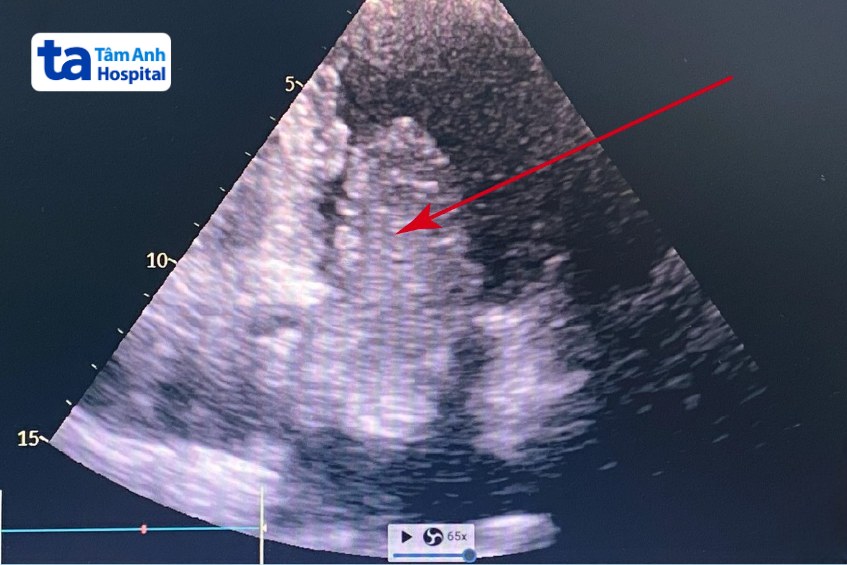

BS.CKI Phạm Thục Minh Thủy, Trung tâm Tim mạch, cho biết kết quả siêu âm tim ghi nhận khối u (nghi là u nhầy) kích thước 11×4 cm nằm ở tâm nhĩ trái, gồm 3 búi dạng thùy dính vào nhau, di động qua van hai lá.

U nhầy (myxoma) là loại u nguyên phát thường gặp nhất ở tim, phần lớn lành tính, và thường khu trú tại tâm nhĩ trái. Trường hợp của bà Hương, bác sĩ Thủy giải thích nếu không điều trị, khối u có thể gây ra các biến chứng nghiêm trọng như hẹp giả van hai lá do khối u lấp lỗ van, tắc mạch dẫn đến đột quỵ, hoặc ngừng tim đột ngột do tắc nghẽn dòng máu tim. Các bác sĩ hội chẩn và phẫu thuật khẩn cho bệnh nhân để tránh nguy cơ đột tử do tắc nghẽn dòng máu trong tim.